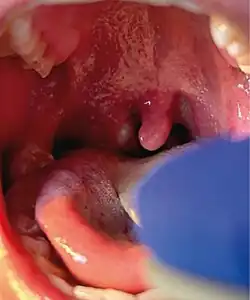

Mpox is a viral infection that manifests a week or two after exposure with fever and other non-specific symptoms, and then produces a rash with lesions that usually last for 2–4 weeks before drying up, crusting and falling off.[10] While mpox can cause large numbers of lesions, in this outbreak some patients experience only a single lesion in the mouth or on the genitals, making it more difficult to differentiate from other infections.[20] In previous outbreaks, 1–3 per cent of people with known infections had died (without treatment). In the 2022–2023 outbreak the rate of death was less than 0.2 percent. Cases in children and immunocompromised people are more likely to be severe.[21]